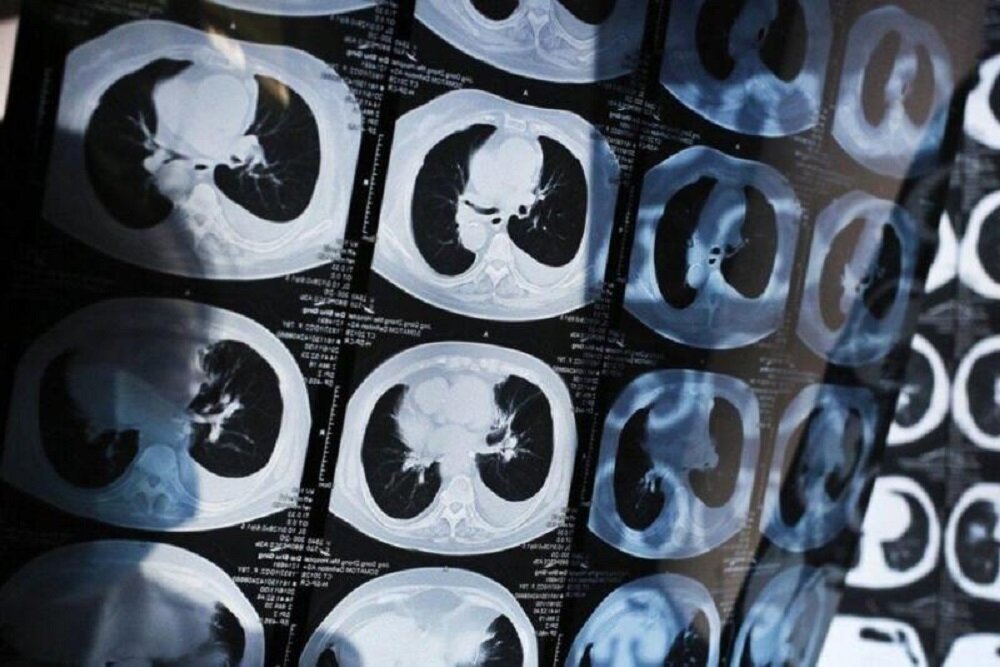

روشی جدید برای تشخیص سرطان ریه در مراحل اولیه ۱۰.۵ | مطالب پیشنهادی (مشابه) | ذخیره شده

۱۶ بهمن ۱۴۰۰ — دانشمندان دانشگاه پکن ابزاری مبتنی بر هوش مصنوعی برای تشخیص سرطان ریه در مراحل اولیه توسعه دادند.

روشی جدید برای تشخیص سرطان ریه در مراحل اولیه ۱۰.۵ | مطالب پیشنهادی (مشابه) | ذخیره شده

۱۶ بهمن ۱۴۰۰ — دانشمندان دانشگاه پکن ابزاری مبتنی بر هوش مصنوعی برای تشخیص سرطان ریه در مراحل اولیه توسعه دادند.

۱۸ شهریور ۱۴۰۰ — بر اساس تحقیقات ارائه شده در کنگره بین المللی انجمن تنفسی اروپا، یک برنامه هوش مصنوعی (AI) می تواند علائم سرطان ریه را در سی تی اسکن یک سال قبل از تشخیص با روش های موجود شناسایی کند.

از پذیرش نخبگان افغانستانی در پارک فناوری پردیس تا شخیص یک سال زودتر سرطان ریه با کمک هوش مصنوعی ۱۰.۳ | مطالب پیشنهادی (مشابه) | ذخیره شده

۱۸ شهریور ۱۴۰۰ — بر اساس تحقیقات ارائه شده در کنگره بین المللی انجمن تنفسی اروپا، یک برنامه هوش مصنوعی (AI) می تواند علائم سرطان ریه را در سی تی اسکن یک سال قبل از تشخیص با روش های موجود شناسایی کند.